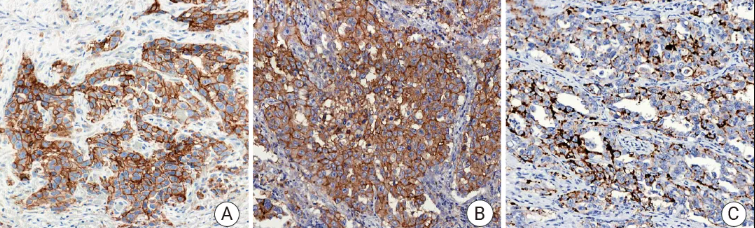

PD-L1

PD-L1——免疫检查点分子,属于 B7-CD28 免疫调节超家族。

• 定位:细胞膜。

• 功能:PD-L1 是一种跨膜蛋白。其主要生理功能是在免疫突触中与免疫 T 细胞表面的 PD-1 受体结合,传递抑制性信号,通过抑制 T 细胞活化和增殖来发挥作用。

肿瘤细胞或肿瘤微环境中的免疫细胞会高表达 PD-L1,与浸润 T 细胞的 PD-1 结合,从而“关停” T 细胞的杀伤功能,实现免疫逃逸。在非小细胞肺癌中,PD-L1 的表达水平是预测免疫检查点抑制剂疗效的关键生物标志物。

图 1. 人肺癌组织的 PD-L1 免疫组化分析。